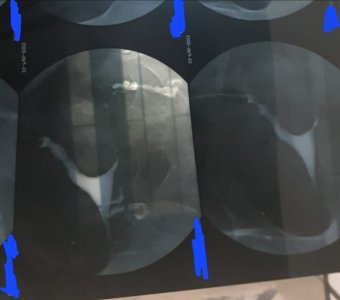

Ya kızlar polikistik over hastasıyım hormon Kilo sorunu asla yok insülin direnci yok.Sperm testimiz rahim filmi temiz.1.5 yıldır evliyim 2 kez gebe kaldım ama pıhtılaşmadan dolayı düştüler sonra öğrendik tabi.Hiç korunmadım 1.5 yıldır.ya benim merak ettiğim norml insalar istediği zaman gebe kalıyorken bizm neden her ay femara kullanıpher ay 2 yumurta oluşmasına rağmen neden ama neden döllenme olmaz?en azından biri döllenme ya.neden doktorlar bişey demiyor